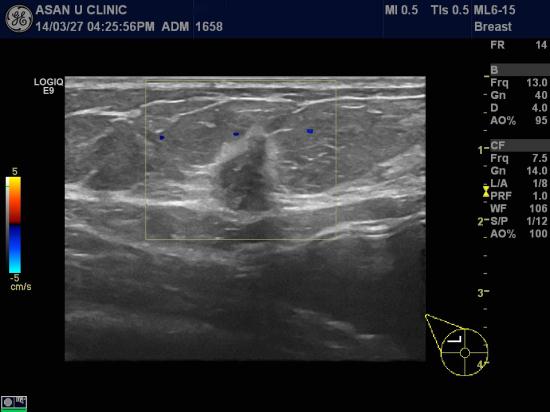

아산유외과 개원 후 83번째 유방암진단.

건강검진상 이상소견으로 내원한 46세 여성분입니다.

우측 유방에 종괴 있었고 겨드랑이에는 다행히 암전이 소견은 보이지 않습니다.

중심핵생검으로 침윤성 유관암 진단되셨지만,

암의 크기가 크지 않아 매우 좋은 예후를 보입니다.

건강검진 덕에 조기진단이 된 행복한 증례입니다.